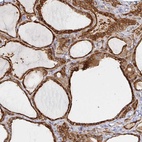

Immunohistochemical staining of human thyroid gland shows strong cytoplasmic positivity in glandular cells.